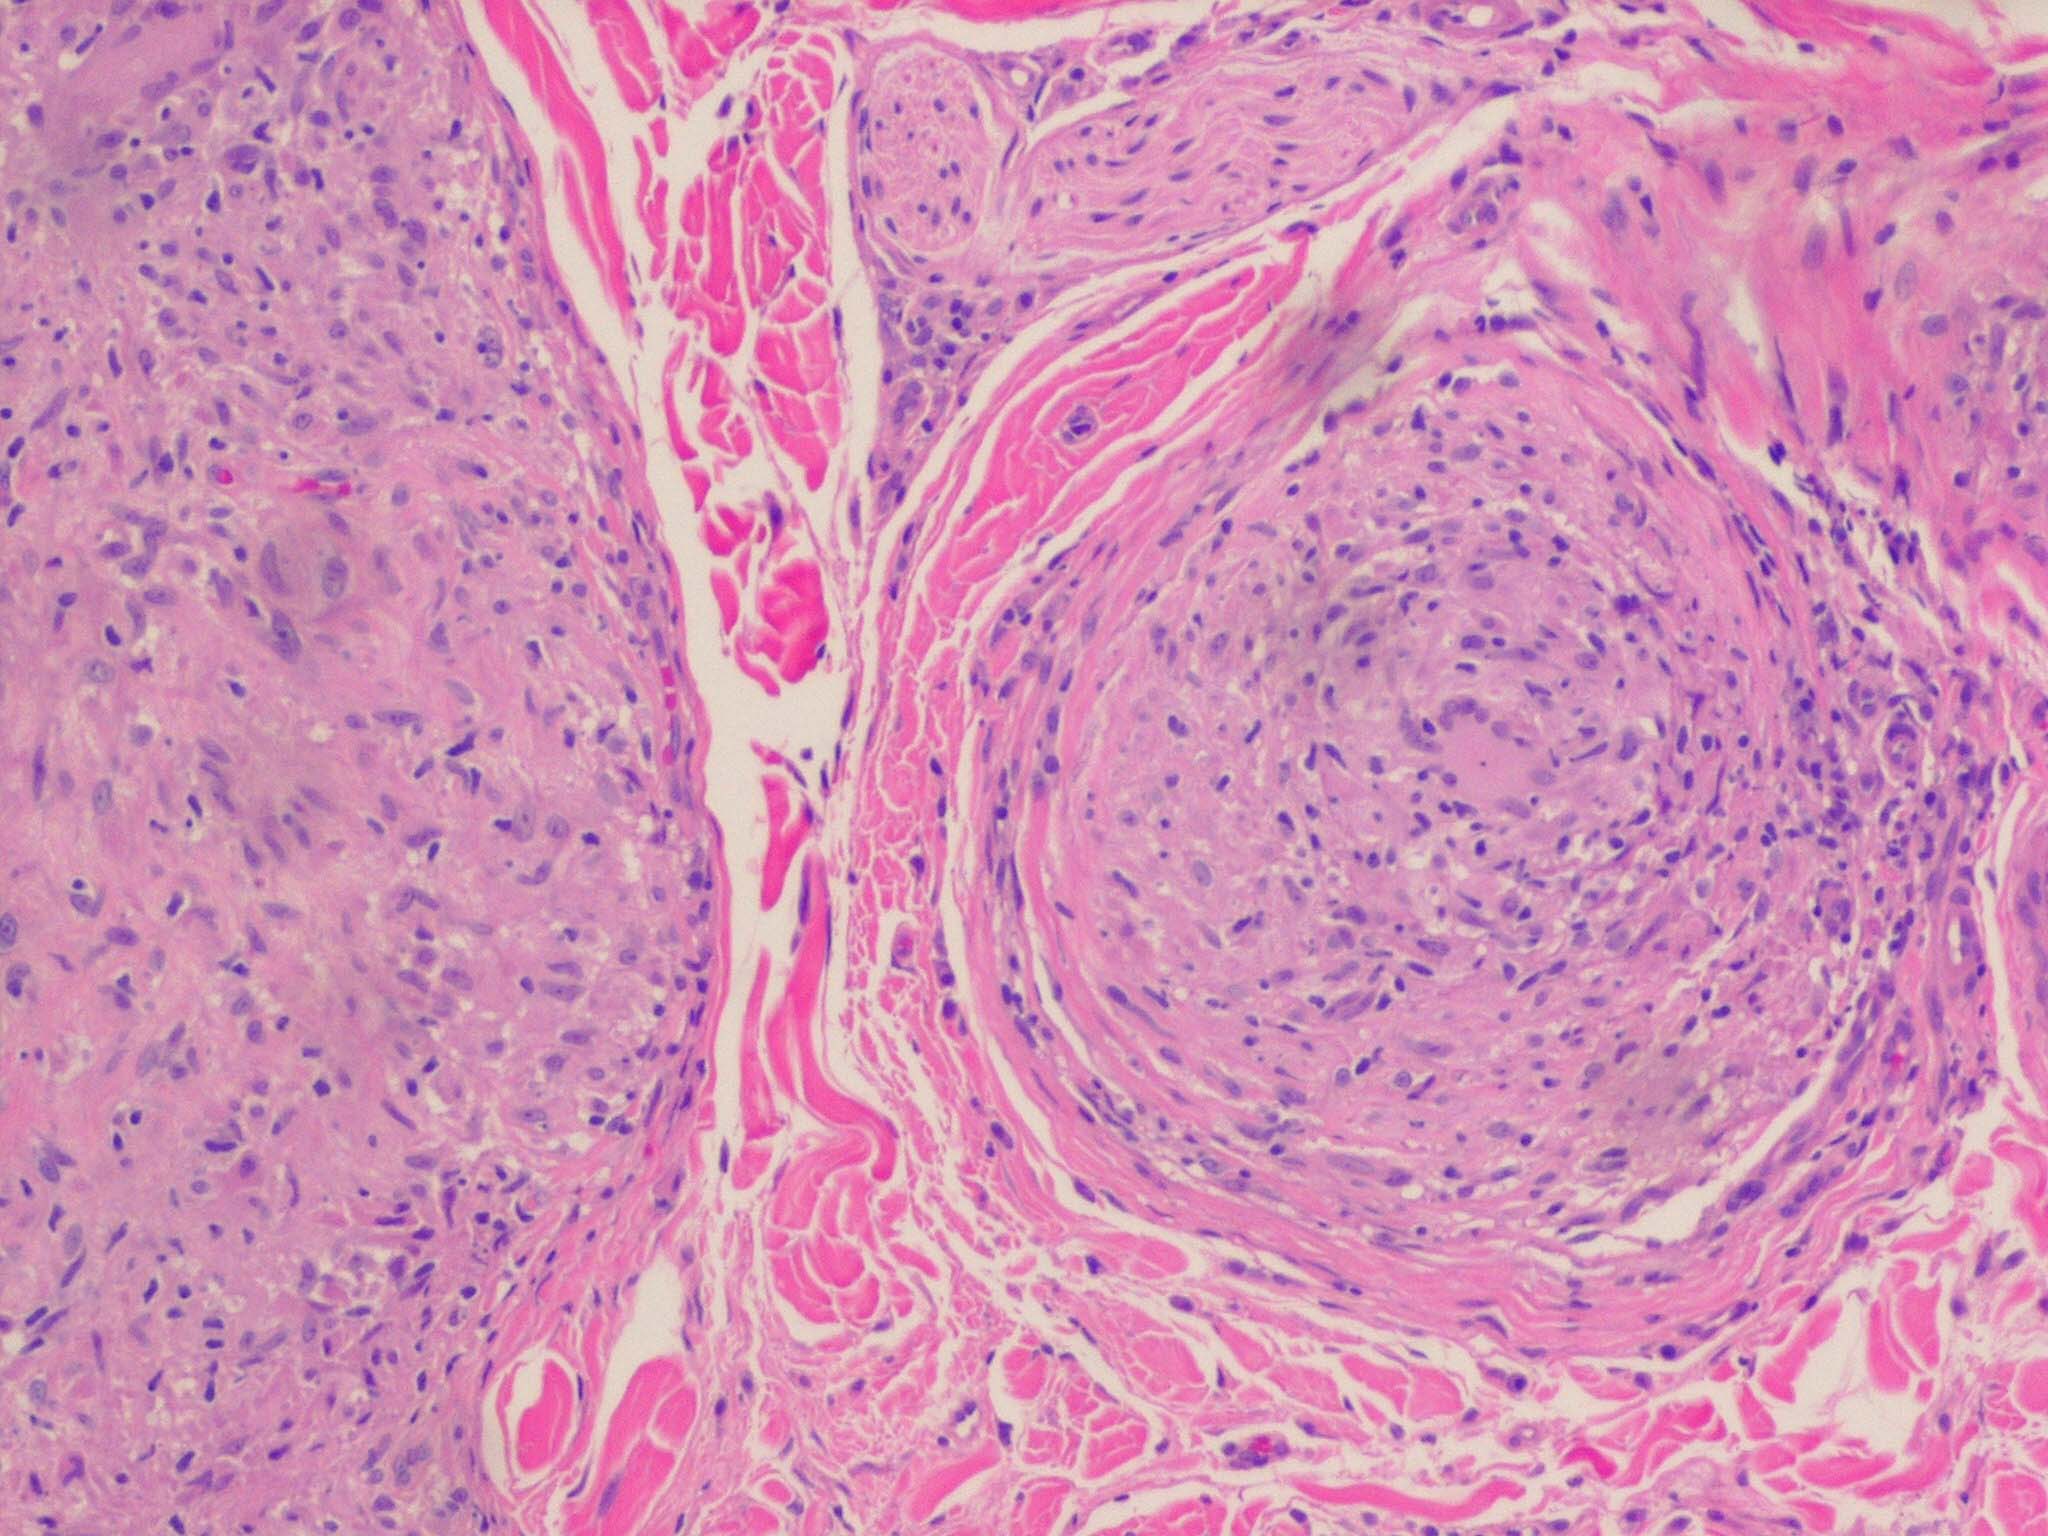

In typical cutaneous lesions of sarcoidosis, the well-demarcated islands of epithelioid cells contain few, if any, giant cells. Those that are present are usually of the Langhans type. A moderate number of giant cells can be found in old lesions. These giant cells may be large and irregular in shape. In a minority of cases, giant cells contain asteroid bodies or Schaumann bodies . Asteroid bodies , which are more common, are star-shaped eosinophilic structures that, when stained with phosphotungstic acid-hematoxylin, produce a center that is brown-red with radiating blue spikes . Schaumann bodies are round or oval, laminated, and calcified, especially at their periphery. They stain dark blue because of the presence of calcium. Neither of these two bodies is specific for sarcoidosis: They have been observed in a variety of other granulomas, including those of leprosy, tuberculosis, foreign-body reactions, and necrobiotic xanthogranuloma .

Classically, sarcoid has been associated with only a sparse lymphocytic infiltrate, particularly at the margins of the epithelioid cell granulomas . Because of the scarcity of lymphocytes, the granulomas have been referred to as “naked” tubercles. However, lymphocytic infiltrates in sarcoid may occasionally be dense, as in tuberculosis . Occasionally, small foci of fibrin or necrosis showing

eosinophilic staining is found in the center of some of the granulomas . A reticulum stain of sarcoid reveals a network of reticulum fibers surrounding and permeating the epithelioid cell granulomas. If the granulomas of sarcoidosis involute, fibrosis extends from the periphery toward the center, with gradual disappearance of the epithelioid cells . Fibrosis, however, is minimal to absent in most examples of sarcoidosis, with the exception of the morpheaform variant, where it is prominent {191}. Other features that may sometimes be seen include elastophagocytosis, increased dermal mucin, and lichenoid inflammation .